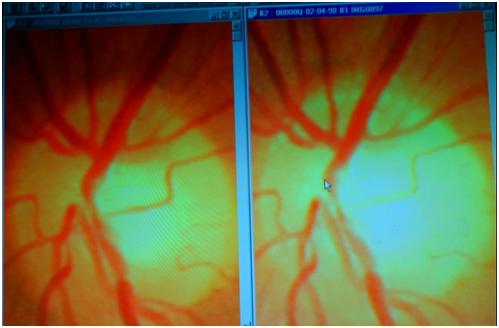

In the “normal” course of events over a period of 16 years, from 1998 to 2014 as shown below, the expected change would be from Left to Right as atherosclerosis develops, circulation deteriorates and death slowly approaches. Here we see the deterioration not only arrested but reversed. All the vessels are functioning better, Neural recovery is evident. Blood flow is greatly improved and if the peripheral vasculature were shown it would be seen to be better perfused with reduced tortuosity of the vessels. The images are of the retinae belonging to author Bush´s older son born in 1956. His fundi now resemble more what we might expect to see in a very healthy 20 year old, and definitely better than we would expect to find in a sportsman engaged in competitive events with corresponding stress. (Figure)